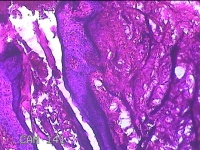

右侧头皮结节

性别

男

年龄

28岁

临床诊断

皮肤良性肿瘤

一般病史

发现右侧头皮结节3个月余,无明显疼痛及不适。

标本名称

大体所见

灰白暗红色组织1.5x1.2x0.8cm一块,表面带梭形皮肤1.5x1cm,皮下见结节1.5x1x0.3cm一个,结节表面有少许毛发,切开结节呈实性,切面灰白粉红色,质软。